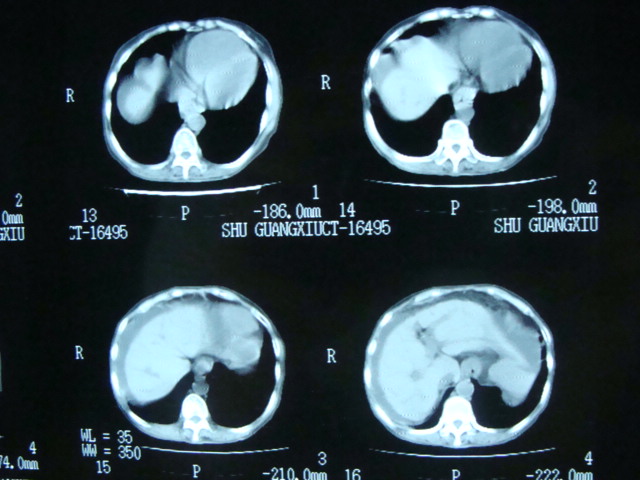

以下是引用liuyue在2008-6-1 18:06:00的发言:[br]1.肺动脉高压,2.腹水。[br]请结合b超。

以下是引用lvji在2008-6-1 17:31:00的发言:[br]肺动脉高压,腹水。